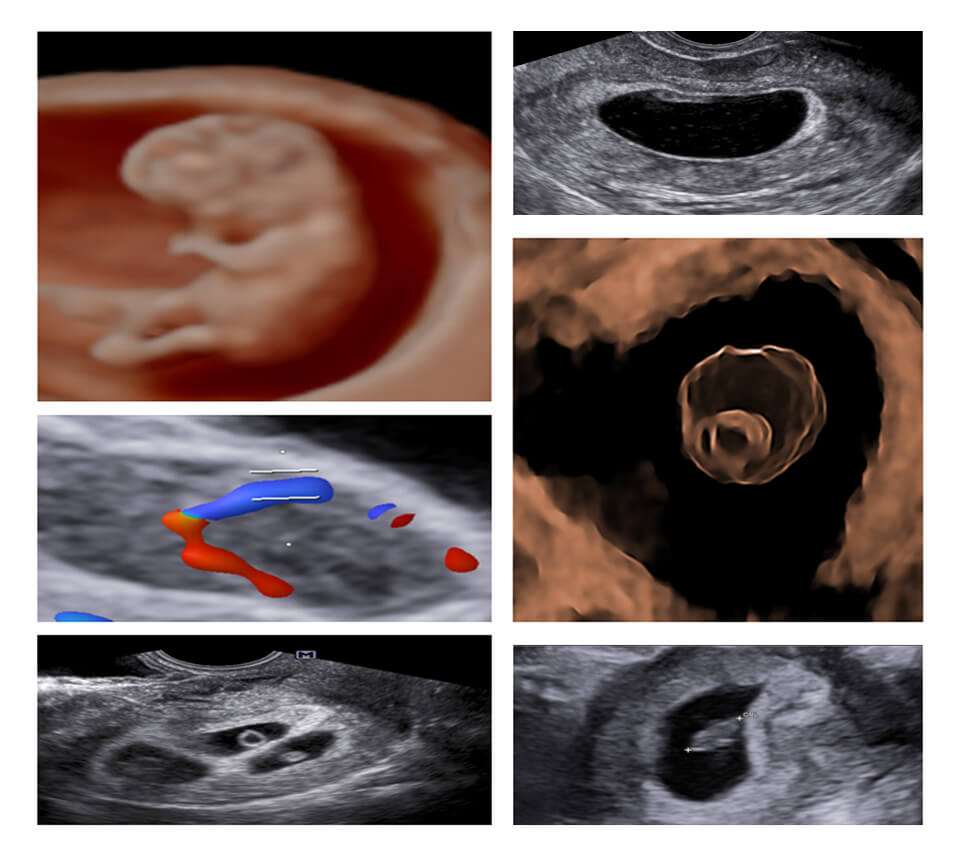

MODULE 3 :- INFERTILITY

CAUSES OF FEMALE INFERTILITY : UTERINE/ OVARIAN/ TUBAL/ ADVANCEMENTS, BASELINE SCAN : 2D/CD : INTERPRETATION AND PLANNING, FOLLICLE MONITORING :2D/CD AND TRICKY SCENARIOS,